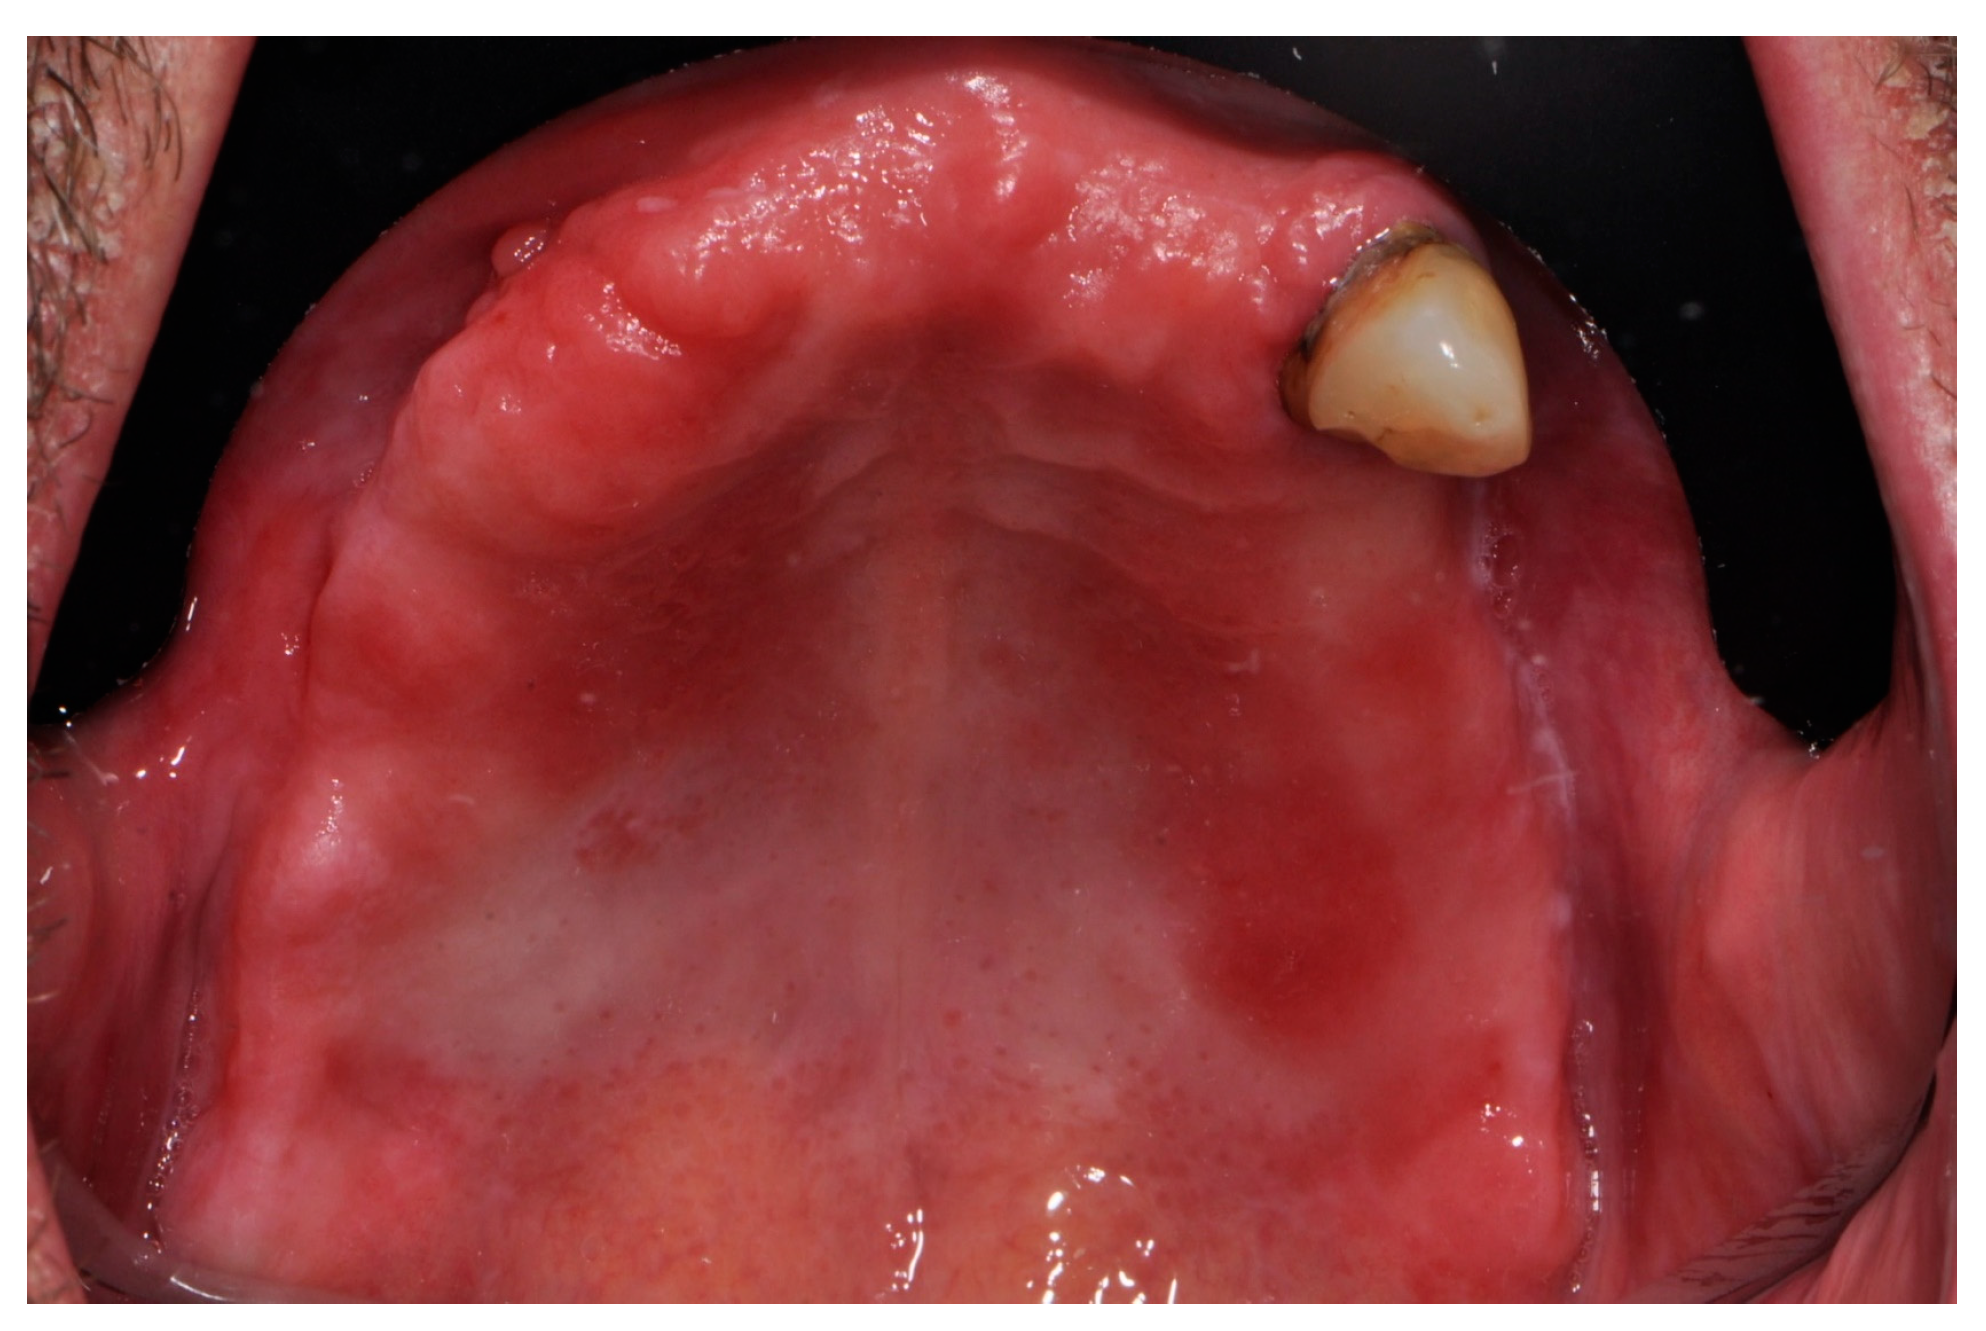

2. Materials and Methods

2.2. Surgical Procedures and Post-Operative Care